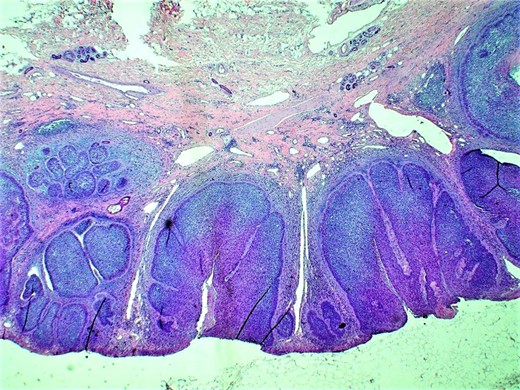

We report a 64-year-old white female with chronic right upper extremity lymphedema secondary to axillary lymphadenectomy after undergoing mastectomy for breast cancer who presents with two distinct skin lesions in the right arm and the forearm. Both of these skin lesions developed 4 year after surgery. Initially, punch biopsy was taken from one lesion, significant for nodular melanoma and the decision was made to excise both lesions. Right arm lymphoscintigraphy was performed using Technetium 99-labeled sulfur colloid with no obvious lymph node enlargement. Intraoperative gamma detection probe could not detect any lymph node activity in the right axilla. Both skin lesion removed during the same surgery with adequate safety margin. The final pathology was consistent with BCC with mixed nodular and superficial patterns in the right upper arm lesion and invasive melanoma with Breslow depth 1.1 mm and Clark level IV in the right forearm lesion. She had uneventful postoperative period and she was followed up clinically with no obvious recurrence (Figs 1 and 2).

Histopathologic examination (H&E; original magnification: 200×) shows small and large nests of basal cell carcinoma within the epidermis and dermis, with typical nuclear palisading at the peripheral layer of the tumor. Picture also highlights dilation of the lymphatic channels within the dermis.